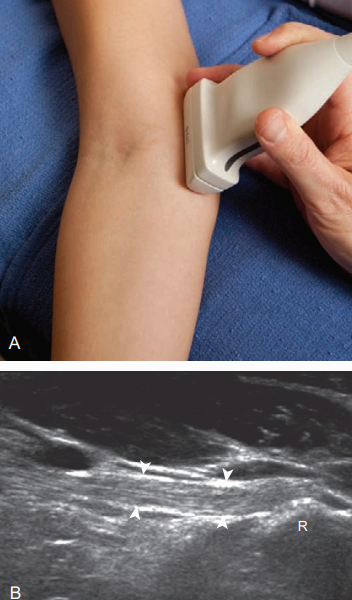

팔꿈치를 펴면 작은 머리의 앞쪽면에서 얇고 균질한 낮은에코의 유리연골을 확인할 수 있다. 작은 머리 위에서 탐촉자를 뒤쪽으로 이동시키면 불규칙한 뼈겉질에 연골이 보이지 않으며 골연골 병변(osteochondral abnormality)으로 오인하면 안 된다. 팔꿈치를 굽히고 탐촉자를 약간 앞쪽으로 이동하면 작은 머리 유리연골의 중앙부위를 검사할 수 있다. 노신경 또한 초음파검사를 통해 효과적으로 평가할 수 있다. 짧은 축영상에서 정상 노신경은 위팔뼈몸통(diaphysis)의 뒤쪽에서 낮은 에코로 보이며 노고랑(radial groove) 내의 노신경이 안쪽에서 가쪽 방향으로 주행하는 것을 확인할 수 있다. 더 아래쪽으로 가면서 위팔노근(brachioradialis muscle)의 깊은 부위로 주행한 후 팔꿈치관절 부위에서 분지 한다. 노신경의 깊은 가지는 손뒤침근의 두 갈래 사이에서 뒤쪽으로 주행하며 뒤뼈사이신경(posterior interosseous nerve)으로 이어진다. 얕은 가지(superficial branch)는 위팔노근 아래로 주행하여 손목으로 이어진다.